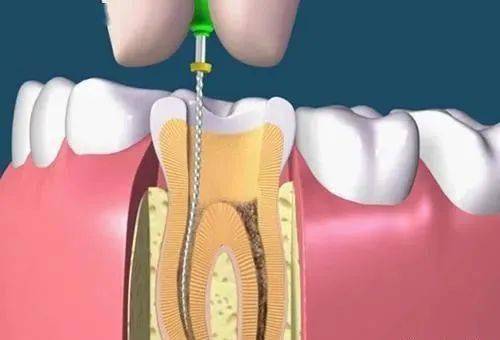

牙齿根管治疗又称为牙髓治疗,根管治疗适应范围较广,牙髓炎,牙髓坏死,各种类型的根尖周炎都适于作根管治疗,包括由于龋齿、隐裂、过度消耗、穿髓等引起的牙髓坏死不能保留... 详情

单纯用材料已经无法恢复功能 因为需要进行根管治疗的牙齿,一般已经是蛀牙缺损很大,这个时候虽然根管治疗完成,但是剩下的牙体组织很少,单纯用材料已经没法补牢实,易脱落。... 详情